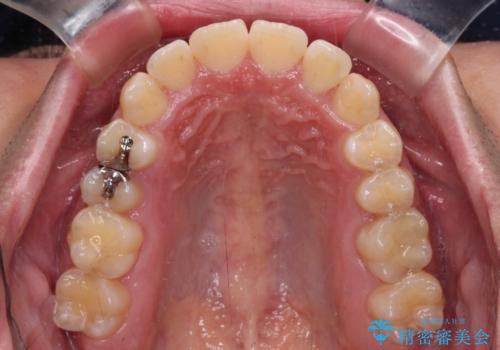

- 上下前歯のデコボコを気にして来院された患者様です。

ワイヤー矯正でもマウスピース矯正でも可能でしたが、短期間で、自身の手を煩わせることなく治療を行いたいとのことで、ワイヤー装置にて矯正治療を行うこととしました。